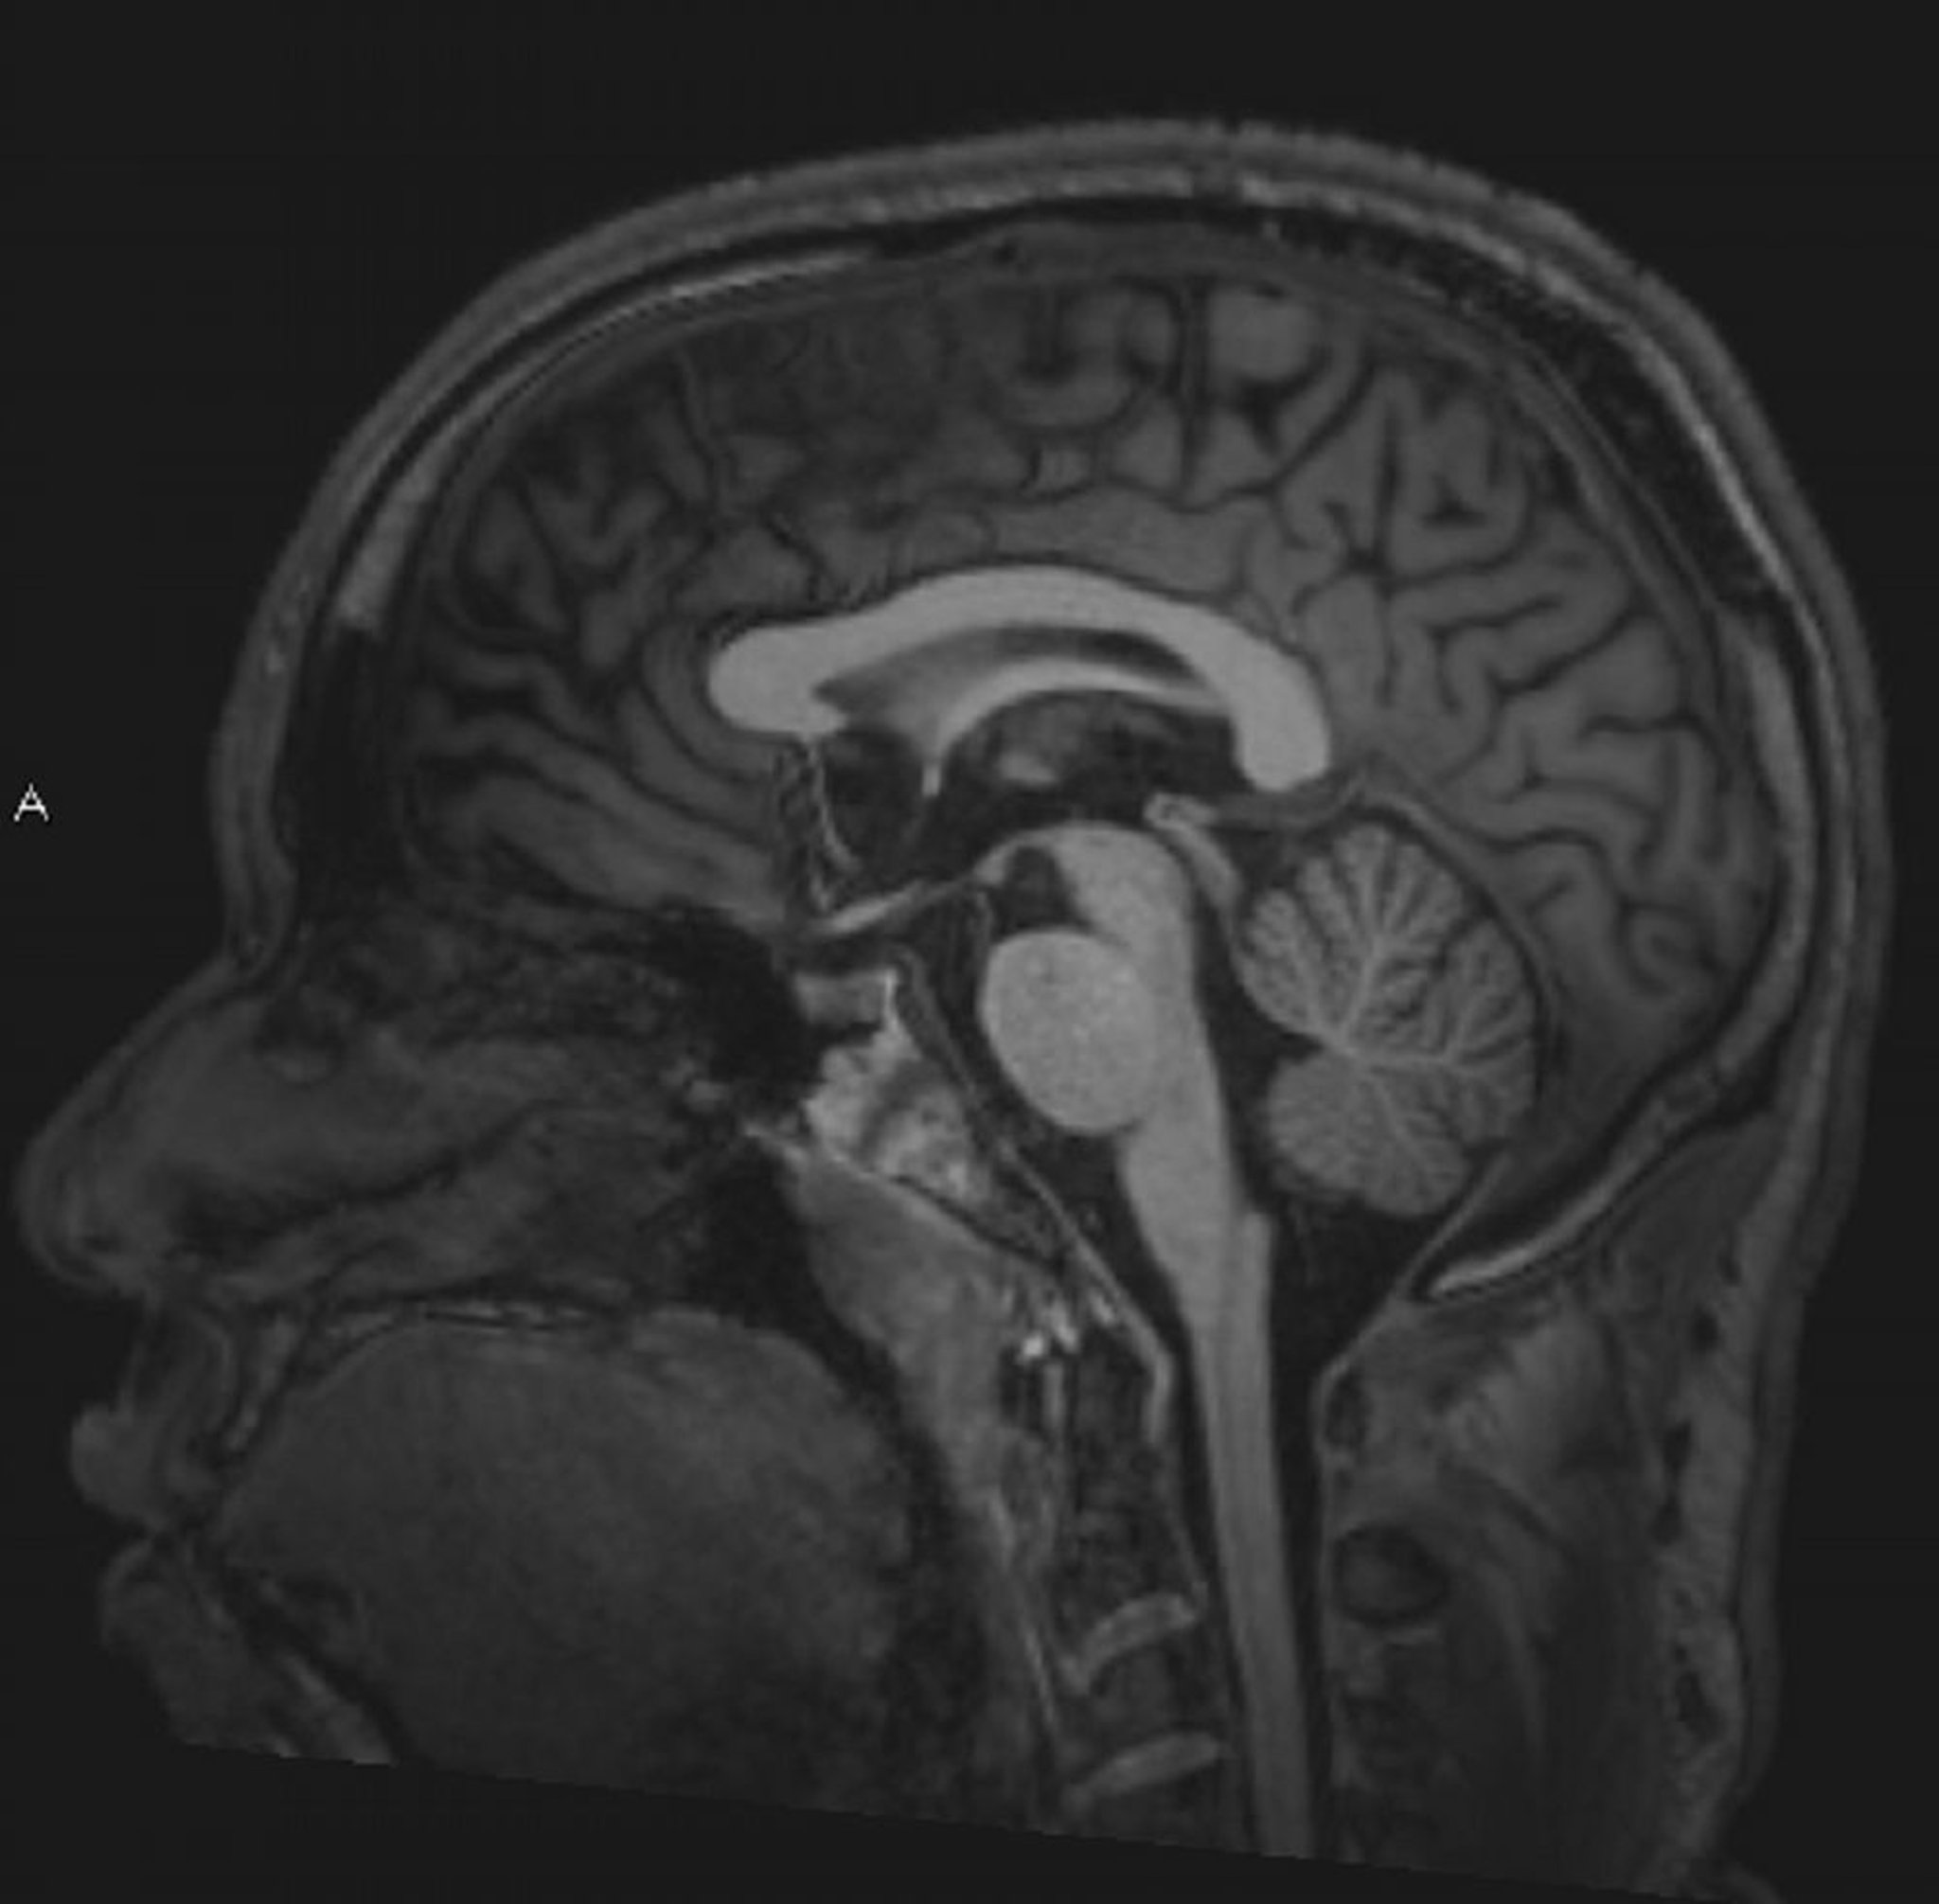

Normal Brain MRI (Sagittal) – Slide 4